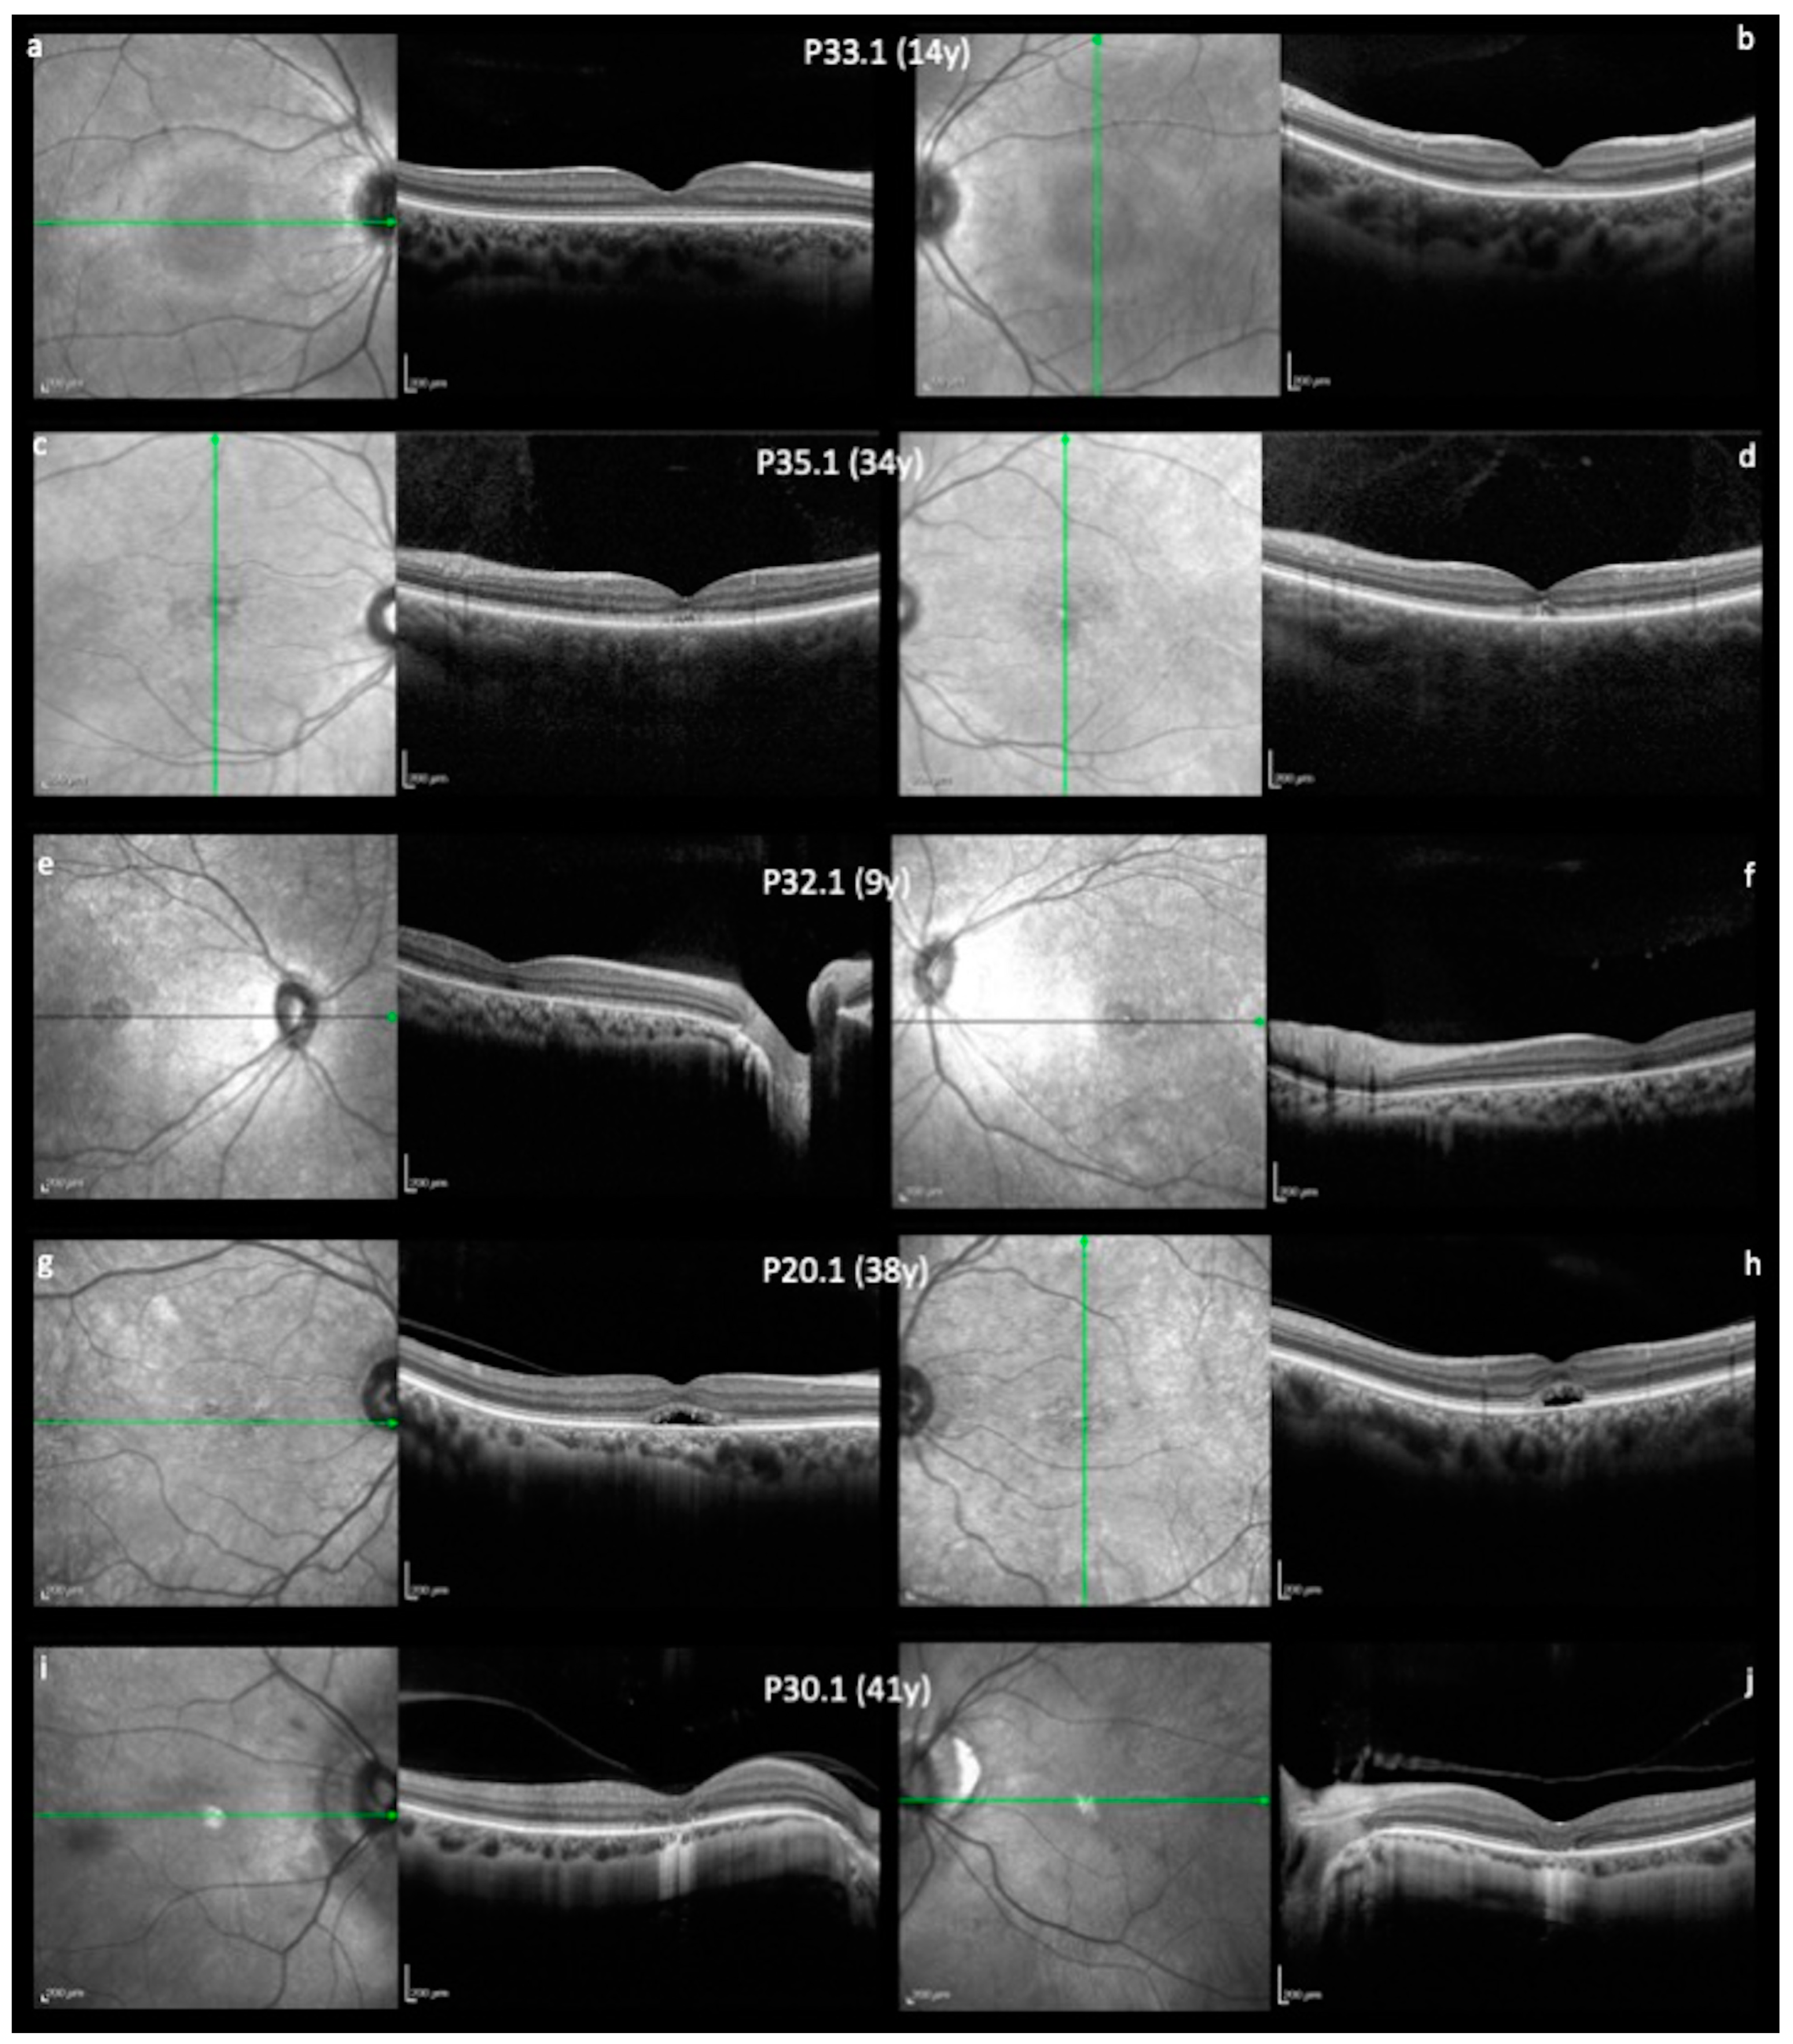

| 33 | 33.1 | 4 months | Nystagmus | 20/160; 20/200 | 1.30; 1.30 | CNGB3 | c.1810C > T (p.Arg604*) | homozygous | pathogenic |

| 35 | 35.1 | 2 months | Nystagmus | N/A | N/A | CNGB3 | c.566G > A (p.Trp189*) | homozygous | pathogenic |

| 32 | 32.1 | Since birth | Nystagmus; photophobia | 20/160; 20/160 | 1.50; 1.55 | CNGB3 | c.1148delC (p.Thr383Ilefs*13) | homozygous | pathogenic |

| 30 | 30.1 | N/A | Nystagmus; photophobia | CF; 20/80 | N/A | CNGB3 | c.446_447insT (p.Lys149Asnfs*30) | homozygous | pathogenic |

| 20 | 20.1 | Since birth | Nystagmus; photophobia | 20/200; 20/150 | 1.60; 1.45 | CNGB3 | c.1148delC (p.Thr383Ilefs*13) | homozygous | pathogenic |